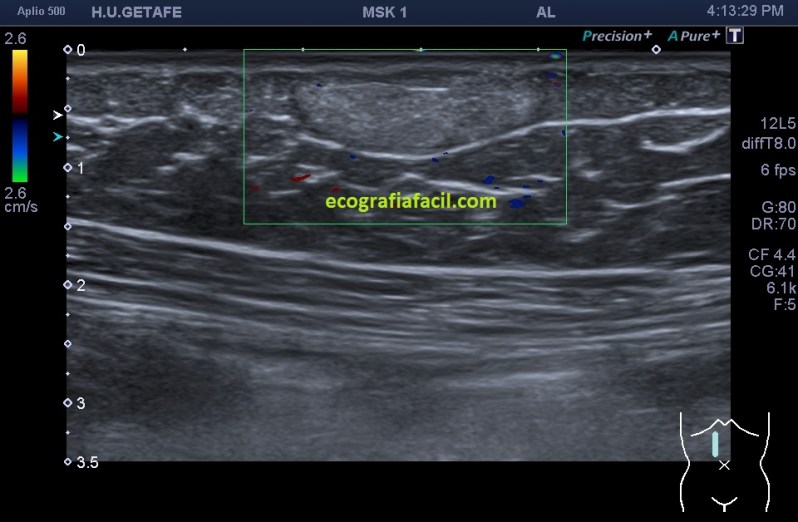

Por otro lado es muy importante la vascularización y el crecimiento de la lesión, ya que estos tumores benignos ni tienen vascularización y su crecimiento es lento.

La vascularización es muy importante, pierde el tiempo necesario en poner todos los doppler que tengas, sobre todo el doppler power, el diagnóstico diferencial entre tener o no tener vascularización (entre otros aspectos semiológicos) podría ser de un liposarcoma, maligno, y por tanto grave. Ojo, que es vital documentarlo para que la radióloga disponga de la información más minuciosa posible.